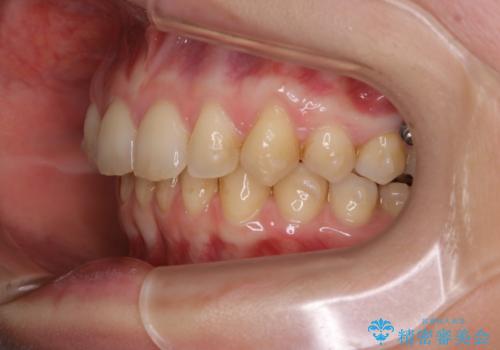

- 着色を落としてほしいとのことで来院されました。

PMTC60分コースを行いました。

着色がとても多くついていました。着色がここまでついていると、目立ちますし、マウスピースをはめたままのお水以外は飲むのは控えましょう。